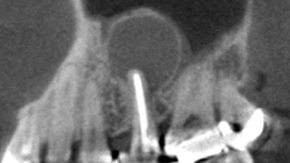

レントゲン撮影を行ったところ、左上5番目の歯の根の先に非常に大きな病変(根尖病変:こんせんびょうへん/根の先にできる炎症)が認められました。

まずは一般的な根管治療(こんかんちりょう/歯の根の中を清掃・消毒する治療)を行いました。しかし、十分な改善が見られなかったため、歯根端切除術を選択しました。

術直後のレントゲンでは、根の先端が切除され、先端部に充填材がしっかり入っていることが確認できました。

Before